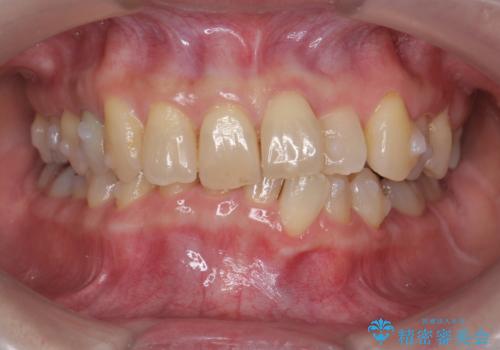

50代女性 インビザライン かみ合わせが深く、難しい症例

かみ合わせが深く、上の歯が咬みこんで下の歯にワイヤーがつけられない状態で、ワイヤー矯正はかなり難しい状態でした。

反対咬合や、すれ違い咬合もあり、大変難しいケースでしたが治療することができました。